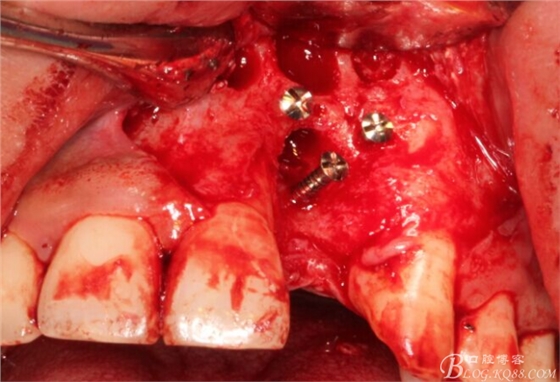

旋入一長(zhǎng)兩短3顆鈦釘。

將自體骨與BIO-OOS骨粉混合植到術(shù)區(qū),蓋生物膜。